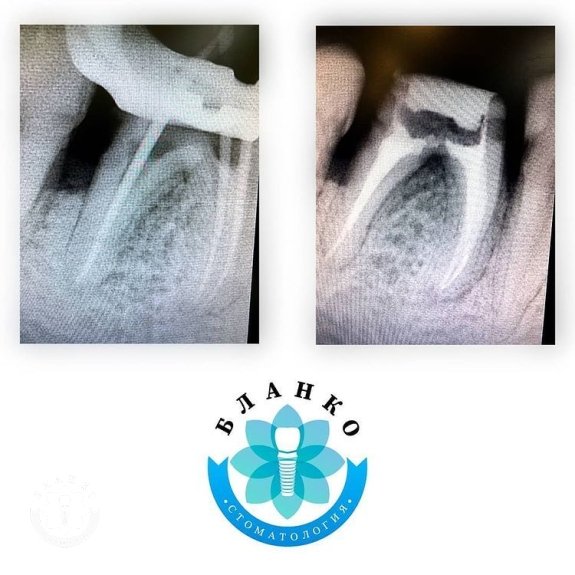

✳️На начальном снимке мы видим зуб 4.6 ( обведен красным цветом ),в котором наблюдается хроническое воспаление вокруг корней зуба и плохая реставрация из пломбировочного материала, которая давно отошла от тканей зуба и под которой развился вторичный кариес ( снимок №2 ).

— распломбированы и пролечены корневые каналы

— запломбированы корневые каналы